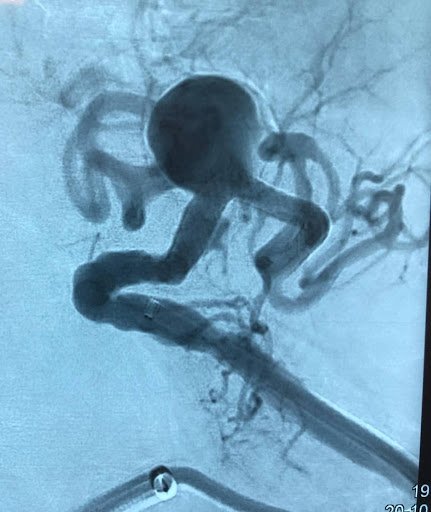

Oclusión de ambas venas ilíacas/Sindrome de congestión pélvica

• Dolor pélvico crónico de origen vascular Evaluación diagnóstica avanzada y tratamiento etiológico orientado a identificar y corregir las alteraciones venosas responsables del síndrome congestivo pélvico y sus manifestaciones clínicas.

• Reconstrucción venosa profunda Tratamiento especializado de obstrucciones iliofemorales, secuelas postrombóticas y enfermedad venosa compleja, orientado a restaurar función y mejorar calidad de vida.

Congestión Venosa Pélvica

Desarrollo y validación del Test de Oclusión de la Vena Gonadal Izquierda para optimizar la indicación terapéutica en pacientes con fenómeno de Nutcracker.

Investigación orientada a mejorar la selección de pacientes para embolización terapéutica.